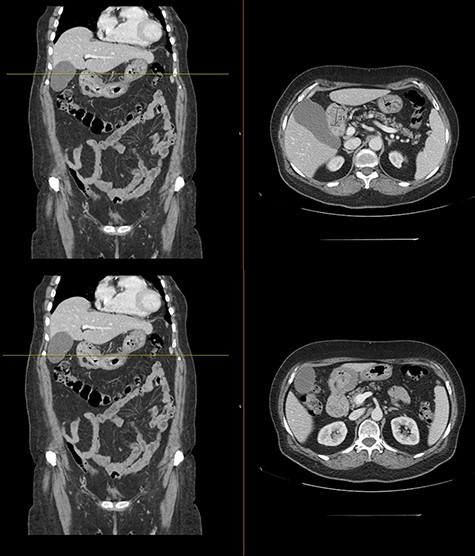

A computer tomography was made to complete the study and showed the presence of endoluminal expansive formations in the gastric antrum as can be seen in Fig. 2.

Computed tomography with intravenous contrast images demonstrating endoluminal expansive formations in the gastric antrum.